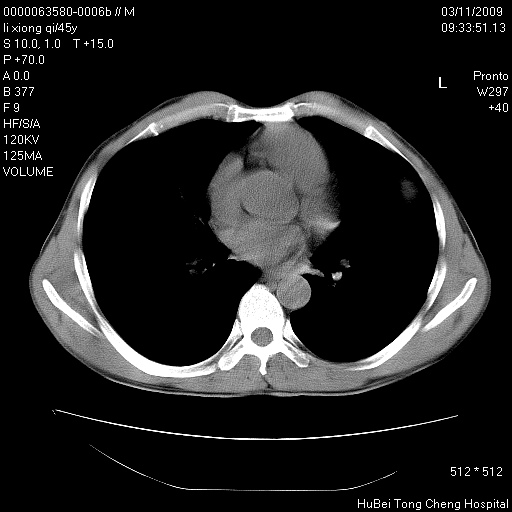

患者 男,45岁。胸痛,咳嗽伴痰中带血1月余。

临床诊断:肺结核?

胸部ct轴位平扫(层厚10mm,螺距1.5,重建间隔10mm),图像如下:

考虑肝癌肺转移

考虑肝癌肺转移。

肝癌肺转移